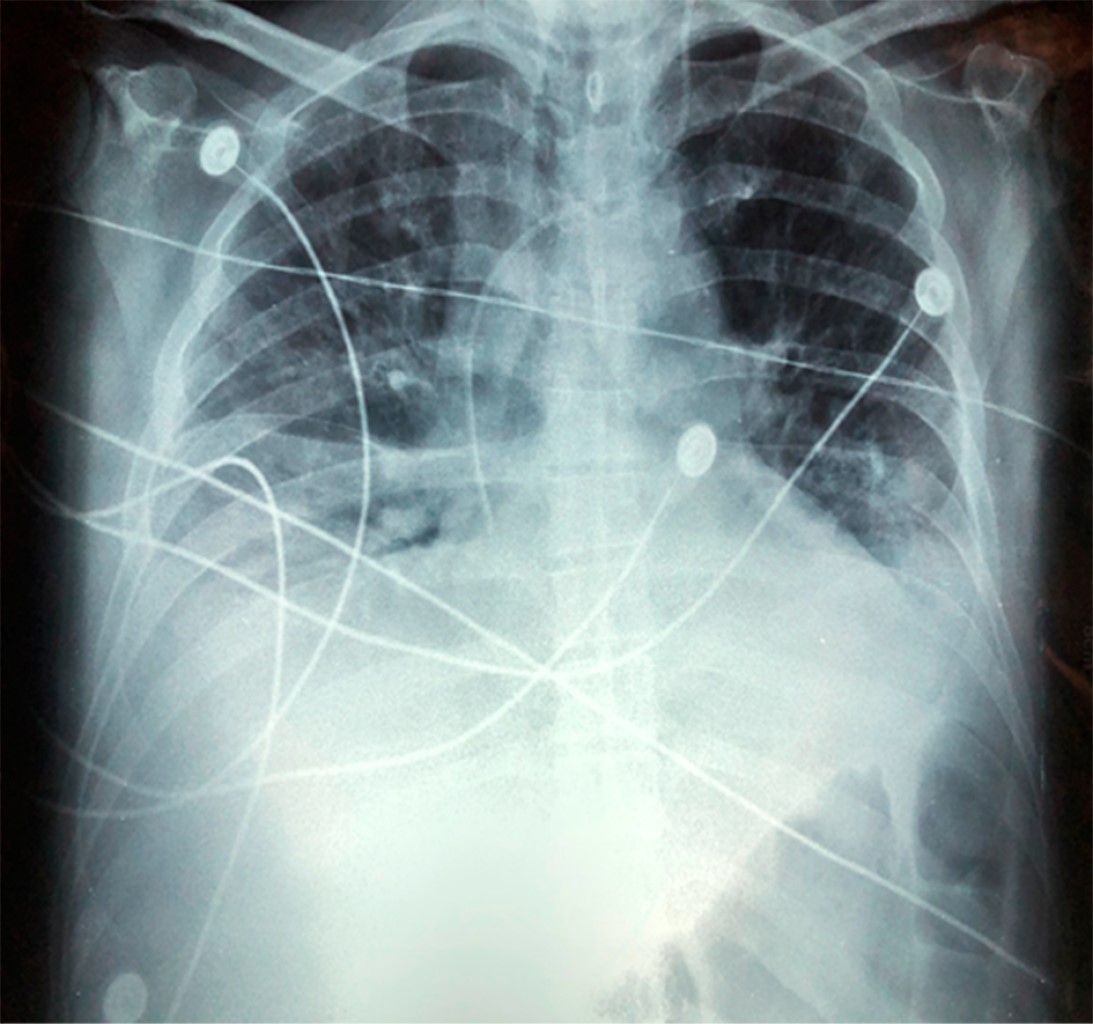

Posteriormente presenta datos de respuesta inflamatoria sistémica y elevación térmica asociándose en un inicio a sepsis abdominal y posteriormente a infección de catéter venoso central. Se realiza cambio del mismo sin mejoría reportando cultivo negativo, a lo cual se añaden estertores bésales y sibilancias. Al sexto día se integra clínicamente el diagnóstico de neumonía, mismo que es confirmado por radiografía de tórax (Figura 1), se solicita cultivo de secreción bronquial y se realiza tomografía toracoabdominal (Figura 2), que revela datos de neumonía asociada al ventilador y se agrega caspofungina al esquema antimicrobiano previo.

Figura 1